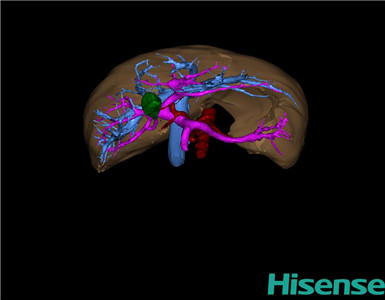

CT结果输入海信CAS系统后行3D重建及手术规划后,于2015-1-8全麻下行“肝脏肿瘤切除术”。

术前三维重建及手术方案设计:

将0.625mm双源薄层CT资料的静脉期和动脉期Dicom格式文件导入海信CAS系统。

通过调节窗宽窗位调整CT序号,对肝实质,胆囊,下腔静脉,肿瘤,肝动脉、门静脉及肝静脉等进行三维重建;系统自动计算肝脏体积。

术前三维重建:

重建图片